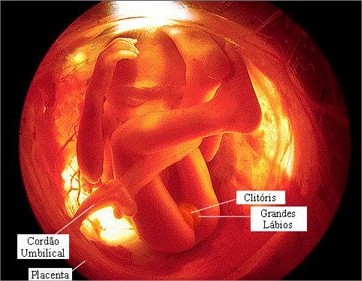

Já na 19ª semana da gravidez, o sistema sensorial do feto está em plena evolução. Uma substância chamada mielina2 começa a se formar na região dos neurônios, ativando as sensações como ouvir sons, sentir cheiros, saborear sabores e sentir toque. É uma fase muito importante, que fará o sistema nervoso funcionar devidamente. Se ainda não sabe o sexo, agora irá conseguir. Afinal, os órgãos genitais já estão completamente desenvolvidos, ficando totalmente visíveis.